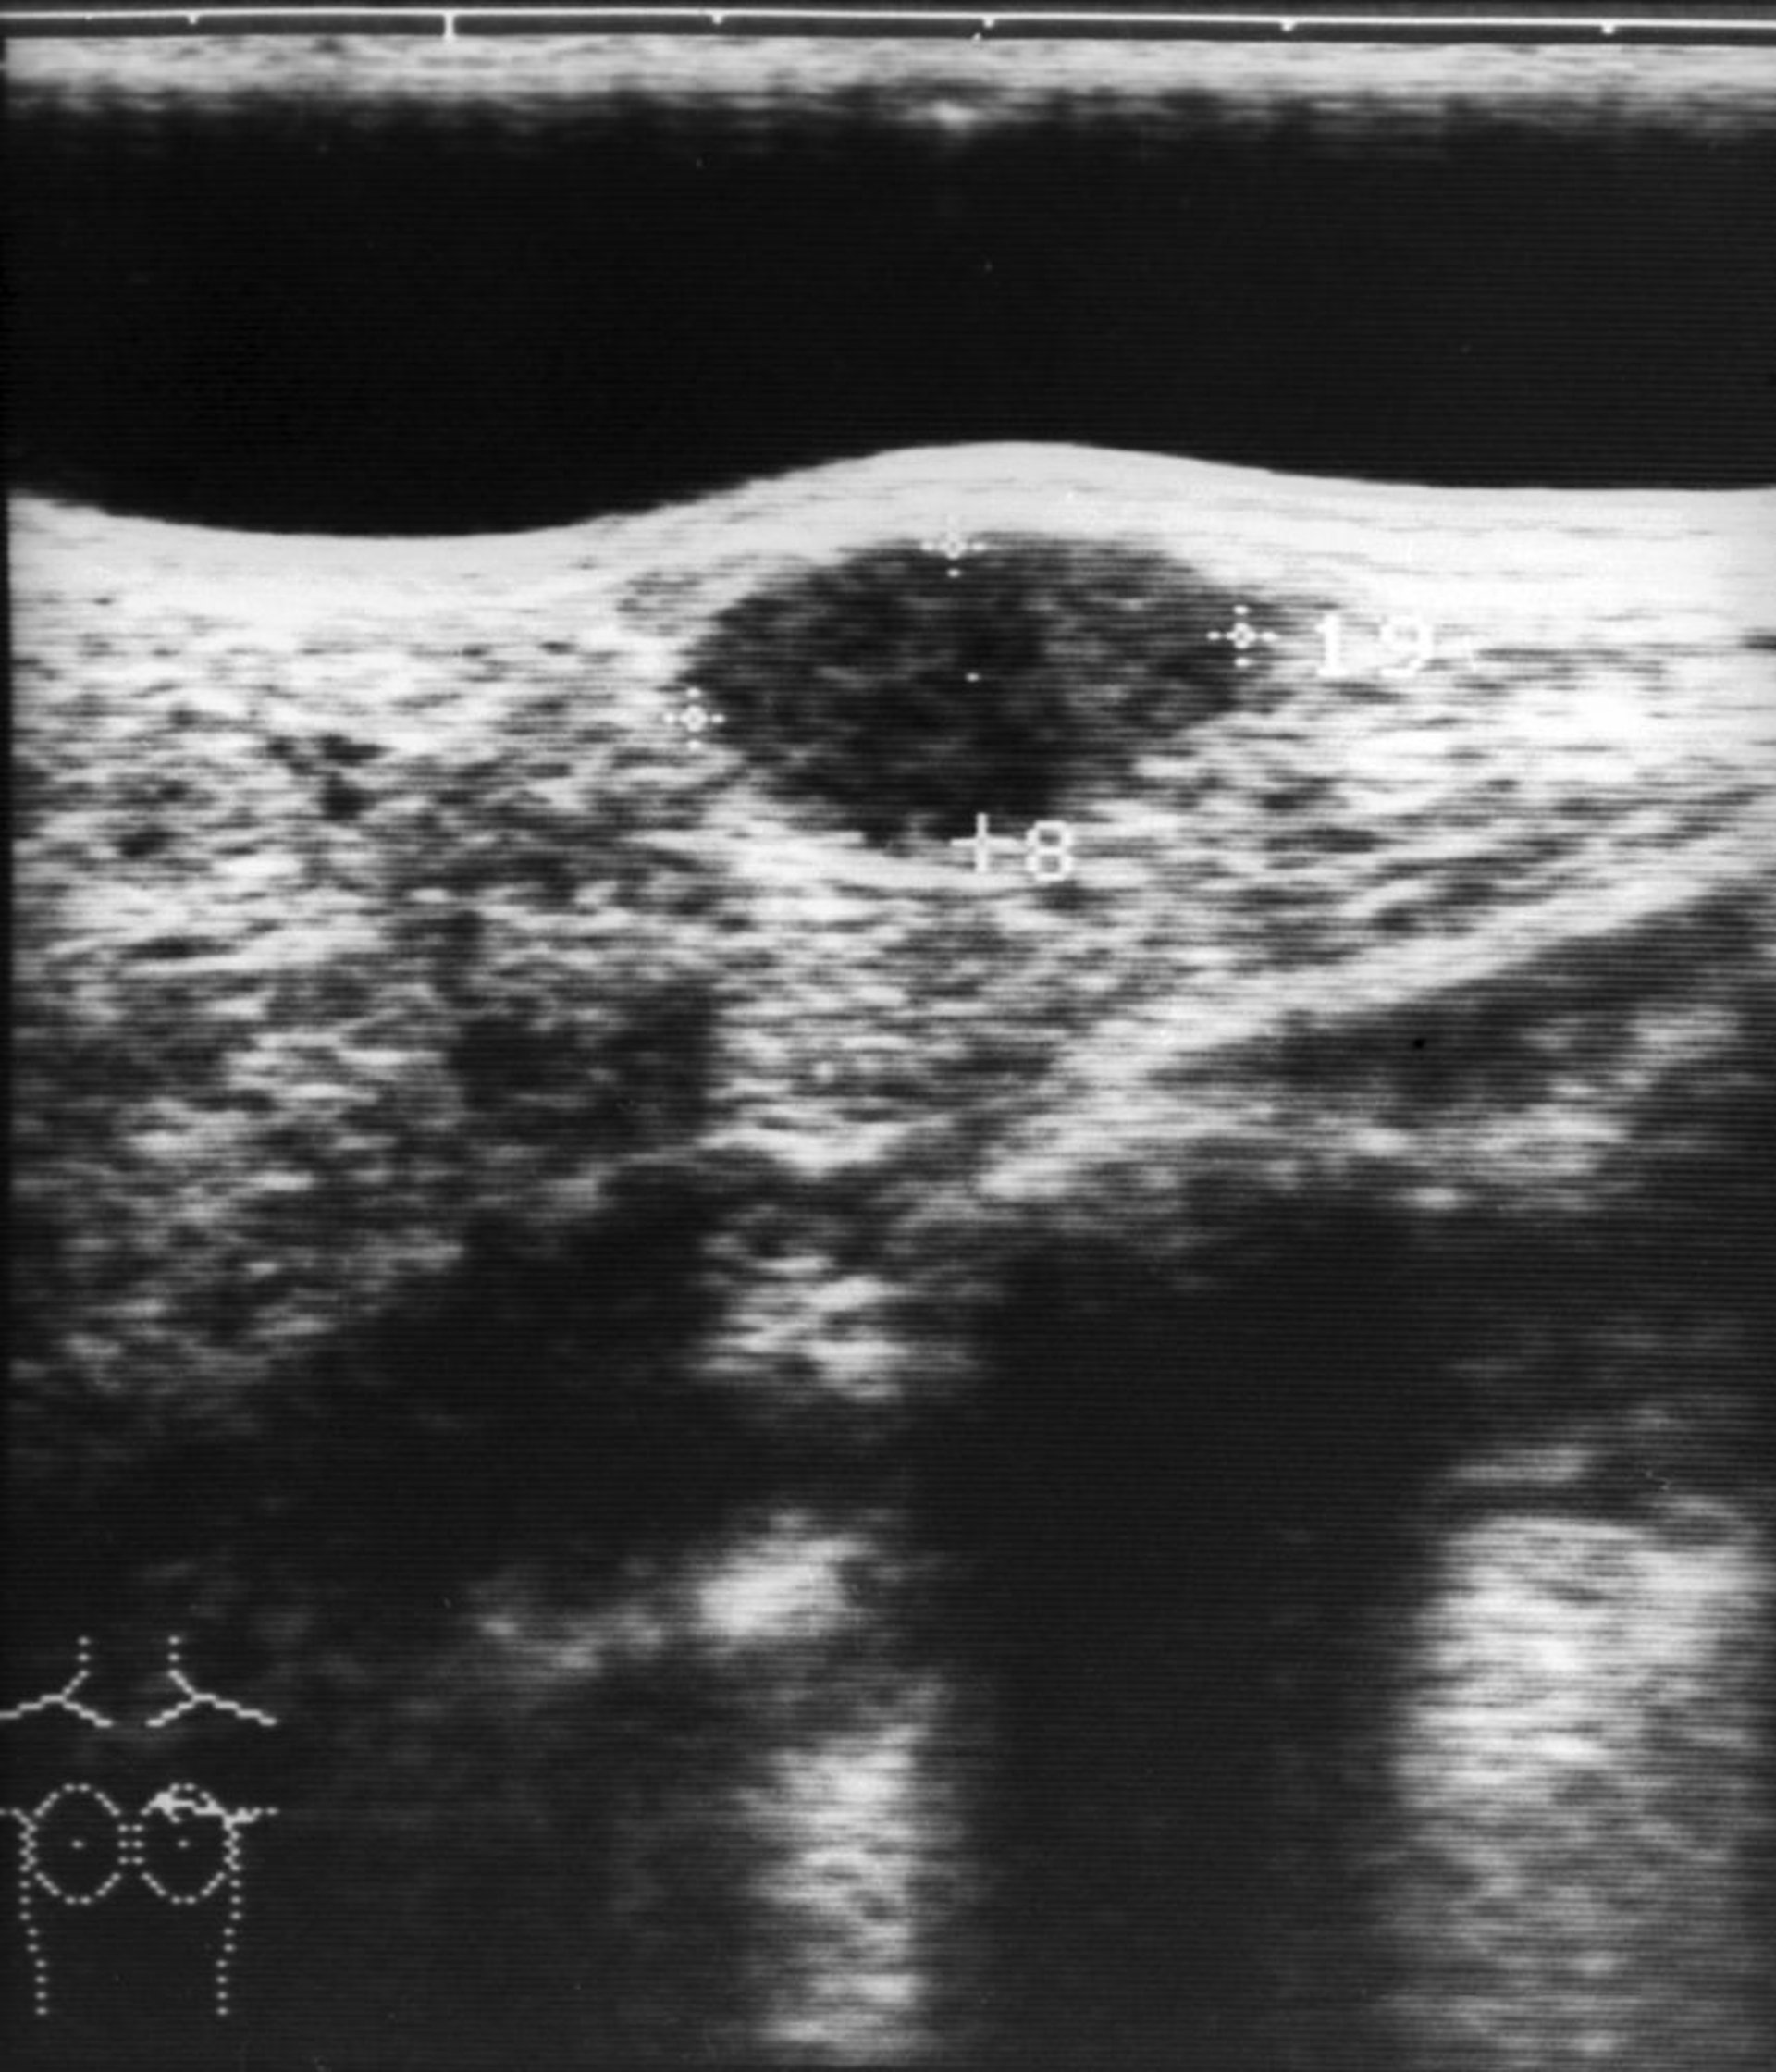

Échographie d'un nodule mammaire

Cette image montre une échographie d'un fibroadénome du sein (structure hypoéchogène ovale dans le centre supérieur de l'image).